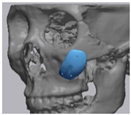

2.2. Computer-Aided Virtual Surgery, Design, and Fabrication of Patient-Specific Devices

2.3. Surgical Procedure

2.5. Cone Beam CT and 3D Comparison